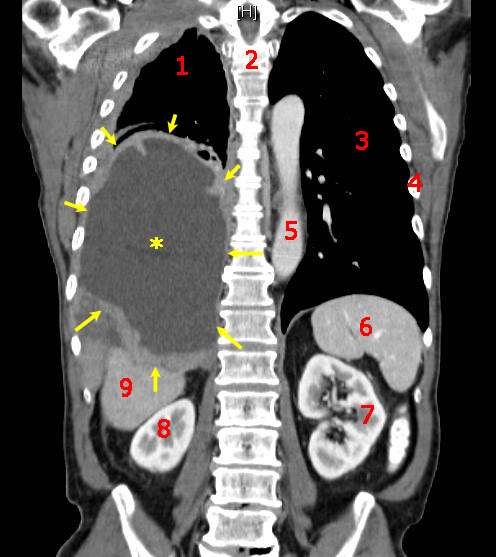

왼쪽 중피종, 종격동 림프절 비대 CT 스캔

왼쪽 중피종과 종격동 림프절 비대를 보여주는 CT 스캔

중피종 환자의 CT 스캔, 시상면(몸을 앞뒤로 나누는 면을 따른 단면). 중피종은 노란색 화살표로 표시되어 있다.

중피종 진단은 증상이 여러 다른 질환과 유사하기 때문에 어려운 경우가 많다. 진단은 환자의 병력 검토부터 시작하며, 석면 노출 병력은 중피종에 대한 임상적 의심을 높일 수 있다. 신체 검사 후 흉부 X선 촬영과 폐 기능 검사를 할 수 있다. X선 촬영에서 석면 노출 후 흔히 나타나는 흉막 비후가 나타나면 중피종에 대한 의심이 증가한다.[15] CT 스캔 또는 MRI를 일반적으로 실시한다.

• 영상 소견: 대부분 X선 검사에서 흉막외 징후나 흉수 축적을 확인할 수 있다. 일반적으로 한쪽 폐에만 나타난다. 흉부 CT에서도 동일한 소견을 얻을 수 있다. FDG-PET에서는 종양의 양성 반응을 확인할 수 있다.